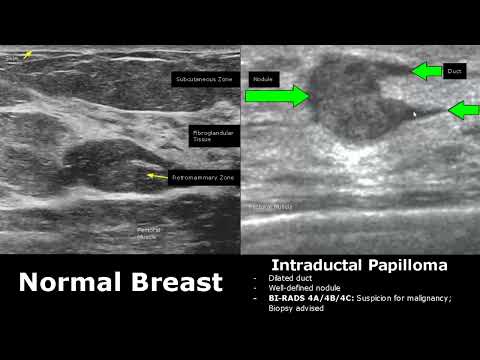

Сравнение нормальных и патологических изображений на УЗИ молочной железы | Классификация BI-RADS